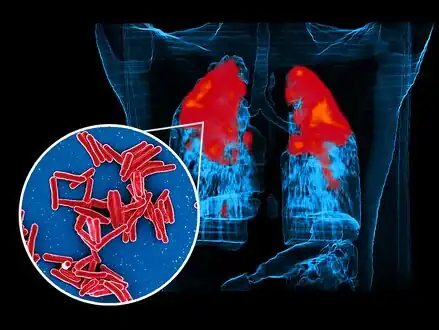

Scanning electron micrograph of Mycobacterium tuberculosis bacteria, which cause TB foreground image and a PET/CT scan showing TB infection (red) in an individuals lungs background image

In active pulmonary TB, infiltrates or consolidations and/or cavities are often seen in the upper lungs with or without mediastinal or hilar lymphadenopathy or pleural effusions ( tuberculous pleurisy). However, lesions may appear anywhere in the lungs. In disseminated TB a pattern of many tiny nodules throughout the lung fields is common - the so-called miliary TB. In HIV and other immunosuppressed persons, any abnormality may indicate TB or the chest X-ray may even appear entirely normal.

Abnormalities on chest radiographs may be suggestive of, but are not necessarily diagnostic of, TB. However, chest radiographs may be used to rule out the possibility of pulmonary TB in a person who has a positive reaction to the tuberculin skin test and no symptoms of the disease.

Cavitation or consolidation of the apexes of the upper lobes of the lung or the tree-in-bud sign[7] may be visible on an affected patient's chest X-ray.[1] The tree-in-bud sign may appear on the chest CTs of some patients affected by tuberculosis, but it is not specific to tuberculosis.[7]

FDG PET/CT

FDG PET/CT can play several useful roles in patients with confirmed or suspected TB.[8] These roles include detection of active TB lesions, assessment of disease activity, differentiation between active and latent disease, assessment of disease extent (staging), monitoring response to treatment, and identification of potential biopsy target.[8]